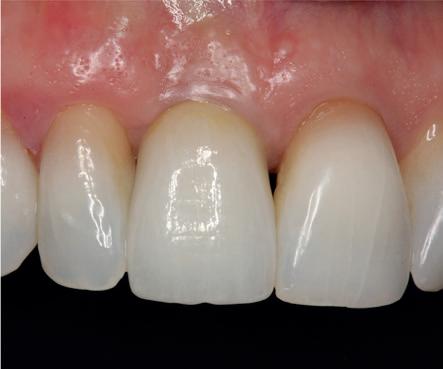

Implantologische behandelingen in het esthetische front vragen meer dan technische vaardigheid alleen. Ze vragen om overzicht, timing, vertrouwen en een team dat als vanzelf samenwerkt onder druk. Juist bij complexe casussen, waarin angst, infectie en hoge esthetische verwachtingen samenkomen, wordt zichtbaar hoe bepalend de rol van de tandartsassistent is.

Deze casus beschrijft een uitgebreide immediate implantaatbehandeling bij een patiënt die door meerdere collega’s werd geweigerd. Niet omdat de mogelijkheden ontbraken, maar omdat de complexiteit vroeg om een perfect afgestemde samenwerking. Het verhaal laat zien hoe de assistent in zo’n traject veel meer is dan een uitvoerende kracht of “mal”, maar een dynamische surgical guide die het proces mede stuurt, bewaakt en mogelijk maakt.De patiënt: wanneer alles samenkomt

Ze kwam binnen op een dinsdagochtend, iets voor achten. Een vrouw van begin zeventig, met een zachte stem en ogen die meer vertelden dan haar woorden. Ze vertelde dat ze een eigen B&B had en dat ze zich nauwelijks kon voorstellen gasten te ontvangen zonder tanden. Op dit moment kon ze echter nauwelijks lachen. “Het doet pijn… en het ruikt soms ook niet goed,” zei ze bijna verontschuldigend. Haar oude bovenbrug, die ze al meer dan twintig jaar droeg, was langzaam maar zeker ingestort. Er was sprake van cariës onder meerdere pijlers, pusafvloed,

chronische ontsteking en een brug die mobiel was en elke beet pijnlijk maakte. Ze had inmiddels meerdere tandartsen bezocht. Drie hadden haar geweigerd. Te complex. Te veel wensen. Te onvoorspelbaar.

De kern van haar vraag was eenvoudig en tegelijkertijd uitdagend: Is het mogelijk om mijn huidige brug te dupliceren en een nieuwe brug te vervaardigen met minder complicaties?